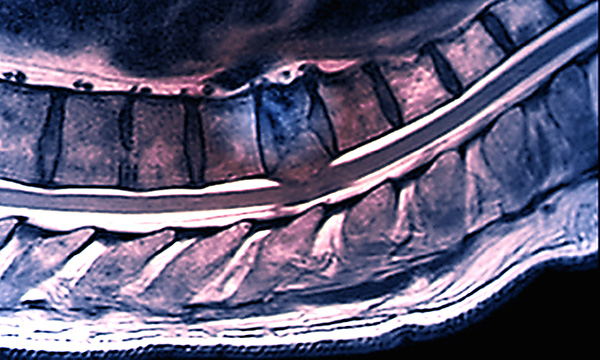

Metastatic spinal cord compression (MSCC) occurs when metastatic disease causes vertebral collapse or compression of the spinal cord or when a tumour extends into the epidural space. It is an oncological emergency which will cause paralysis if left untreated. It is crucial that acute hospital staff recognise ‘red flag’ signs and symptoms of MSCC and adhere to the National Institute for Health and Care Excellence (NICE) guideline on MSCC recognition and management.